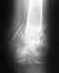

снимок 16.06.11 после установки стержня